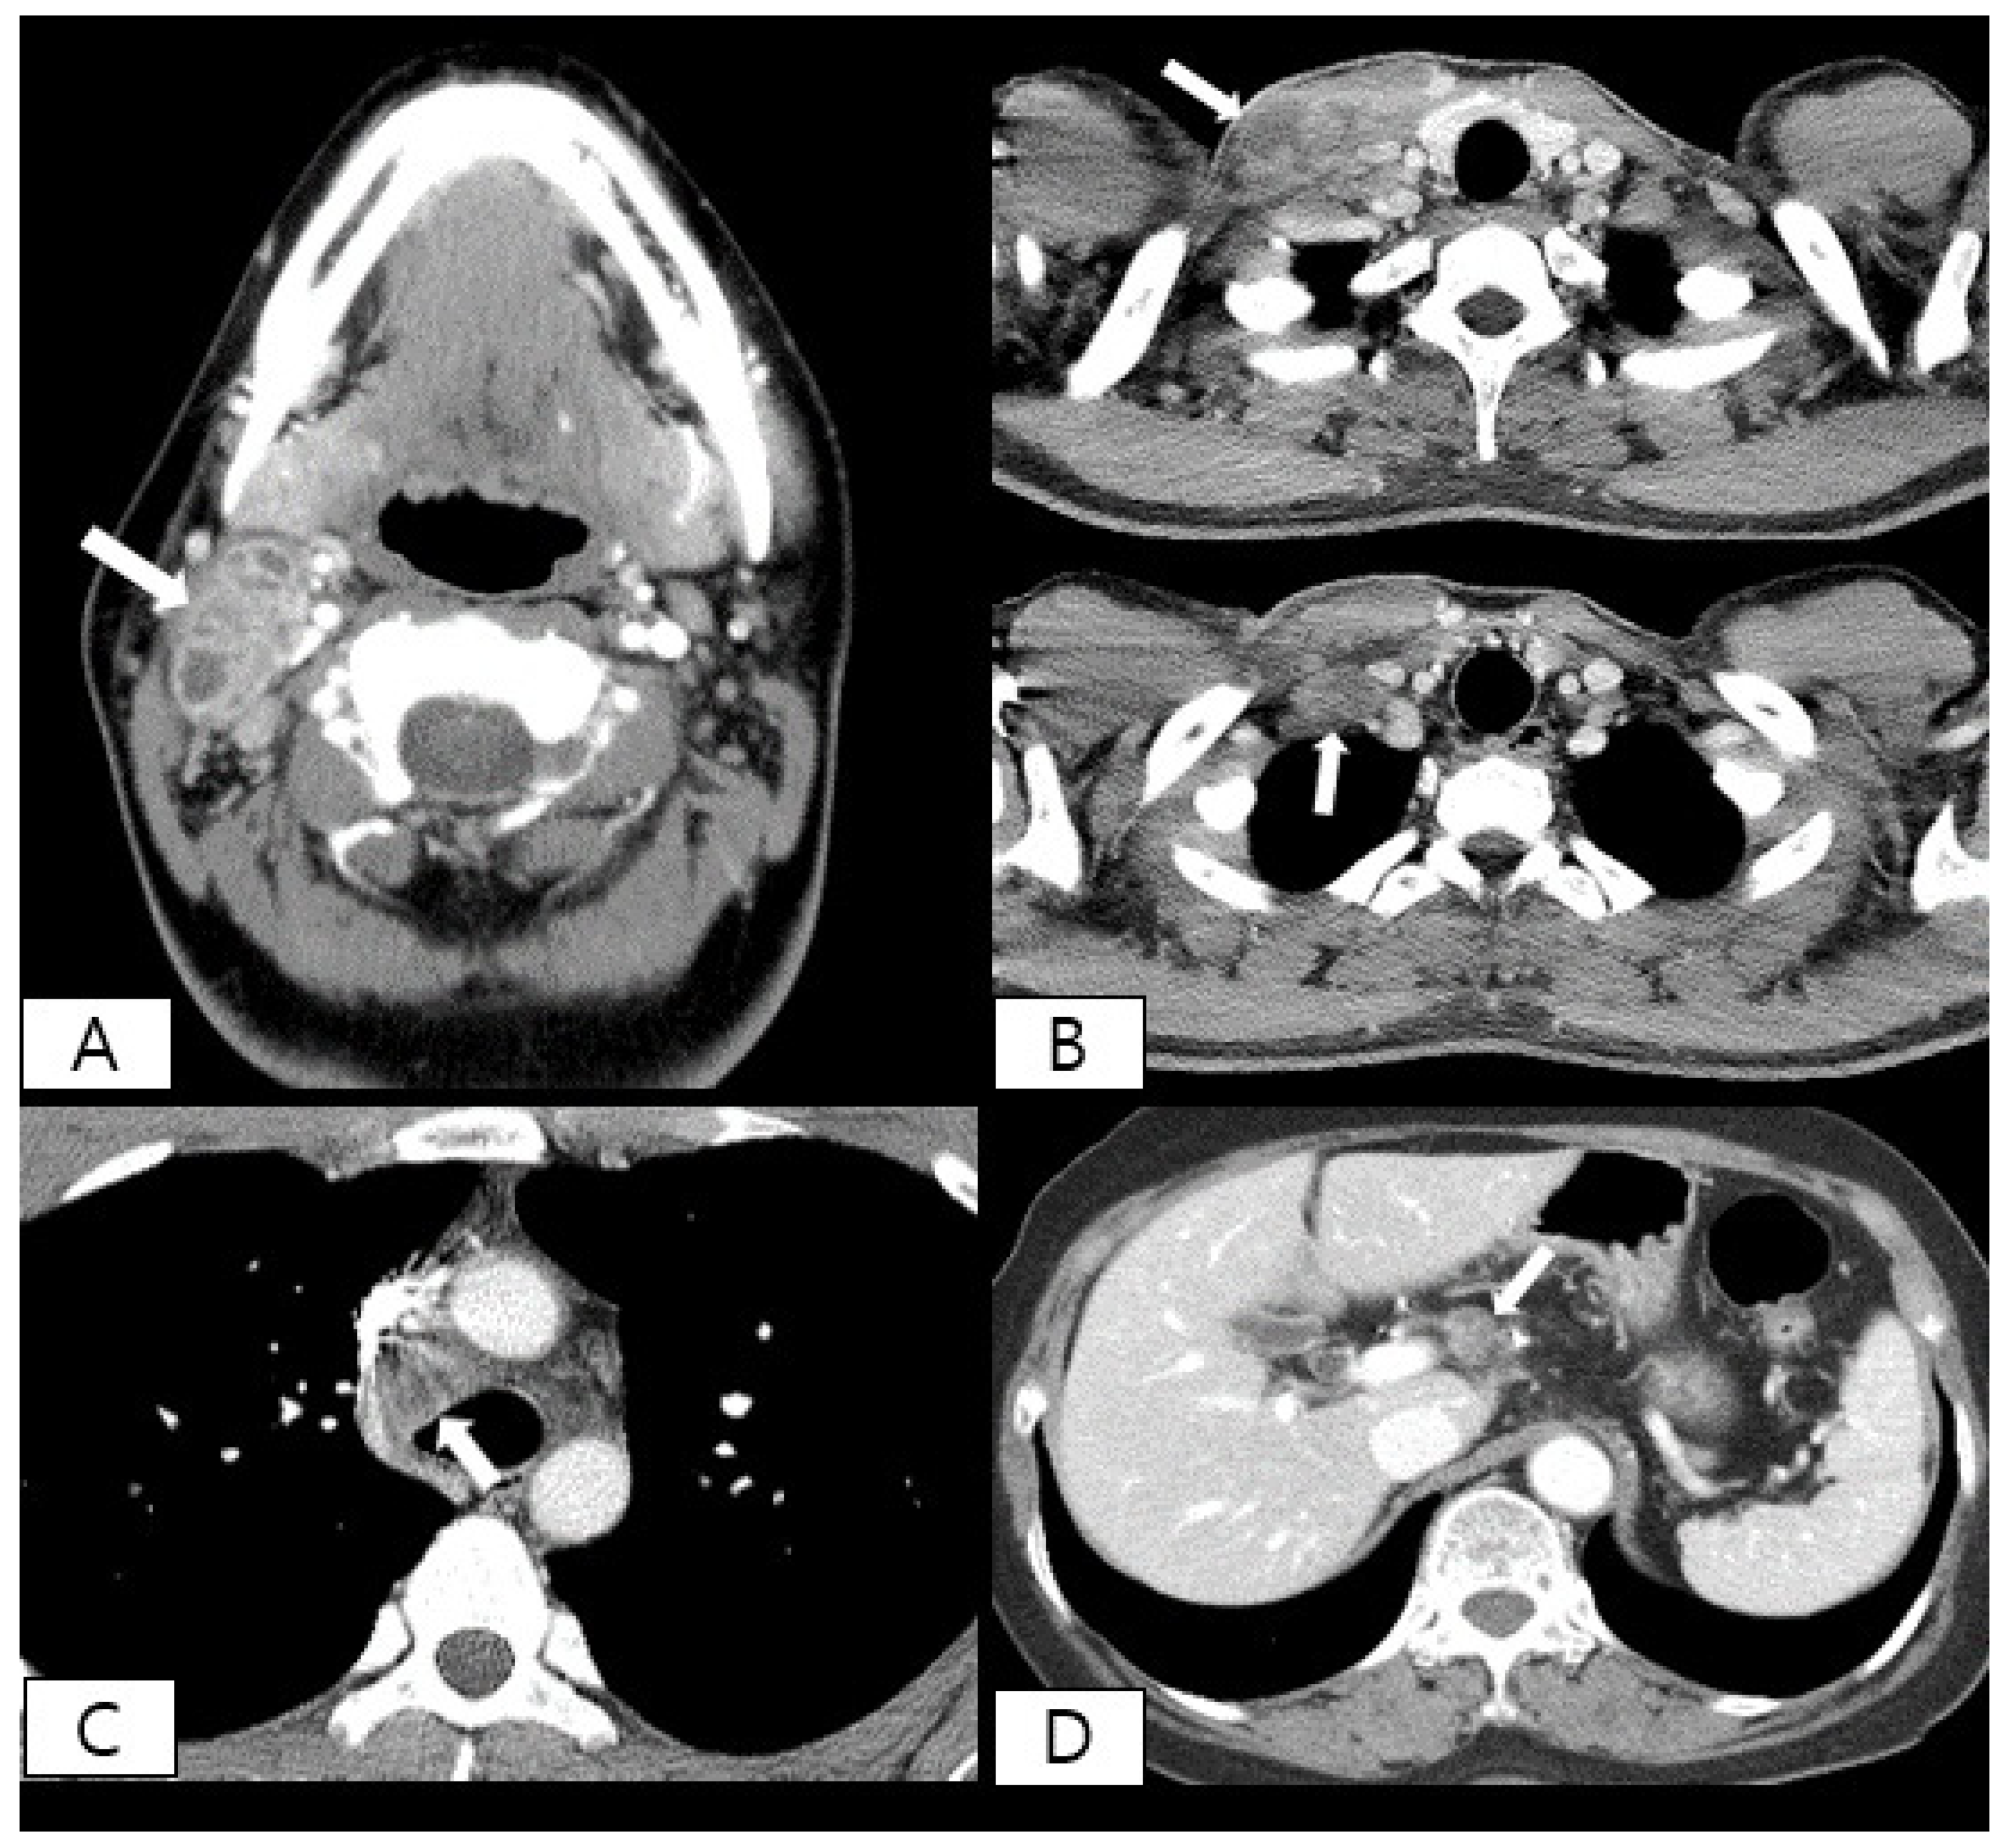

- You, S.H.; Kim, B.; Yang, K.S.; Kim, B.K. Cervical necrotic lymphadenopathy: A diagnostic tree analysis model based on CT and clinical findings. Eur. Radiol. 2019, 29, 5635–5645. [Google Scholar] [CrossRef]